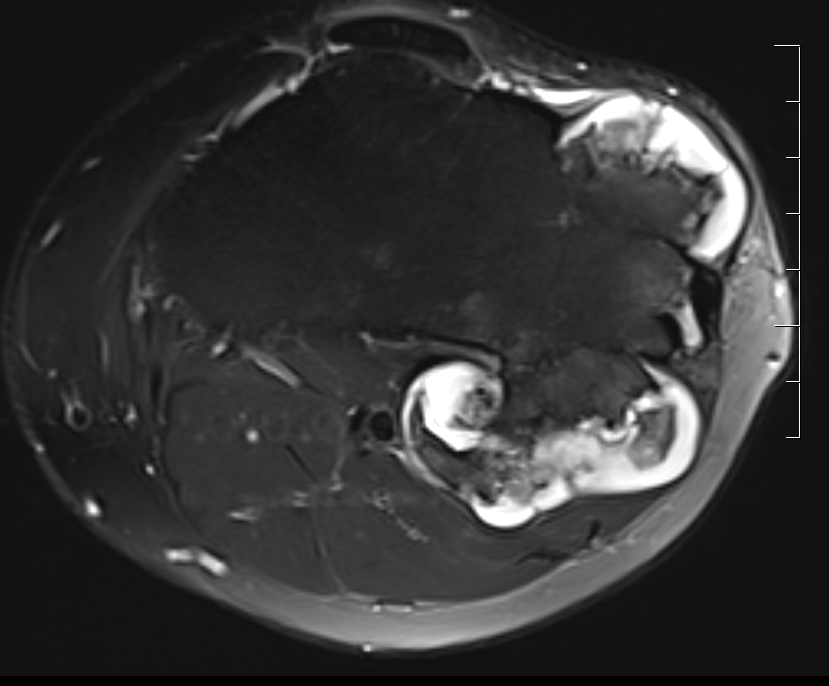

MRI

- MRI of 179 chondrosaroma

- features of high grade chondrosarcoma

- bone expansion, active periostitis, soft tissue mass and increased tumour length